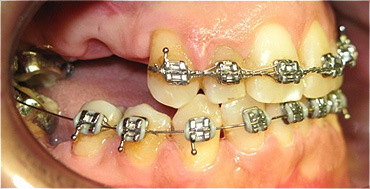

Apinhamento dentário com os dentes caninos em desoclusão (classe II, divisão 2).

![]() |

Após dois anos de tratamento ortodôntico.